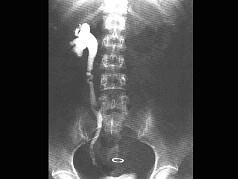

男,25岁,乘车后突然发生右下腹痛,伴恶心,近年来有同样发作史、查体:腹软,右下腹有深腹痛、血常规白细胞9×10/L、尿镜检:红细胞(+++),白细胞06...

问题 男,25岁,乘车后突然发生右下腹痛,伴恶心,近年来有同样发作史、查体:腹软,右下腹有深腹痛、血常规白细胞9×10/L、尿镜检:红细胞(+++),白细胞06个,应诊断为 ( )

选项 A、单纯不完全性肠梗阻 B、右侧输尿管结石 C、美克尔憩室炎 D、右侧输卵管炎 E、慢性阑尾炎急性发作

答案 B